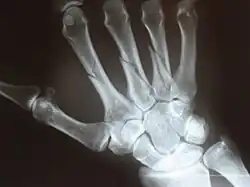

In human anatomy, the metacarpal bones or metacarpus, also known as the "palm bones", are the appendicular bones that form the intermediate part of the hand between the phalanges (fingers) and the carpal bones (wrist bones), which articulate with the forearm. The metacarpal bones are homologous to the metatarsal bones in the foot.

Each metacarpal bone consists of a body or shaft, and two extremities; the head at the distal or digital end (near the fingers), and the base at the proximal or carpal end (close to the wrist).